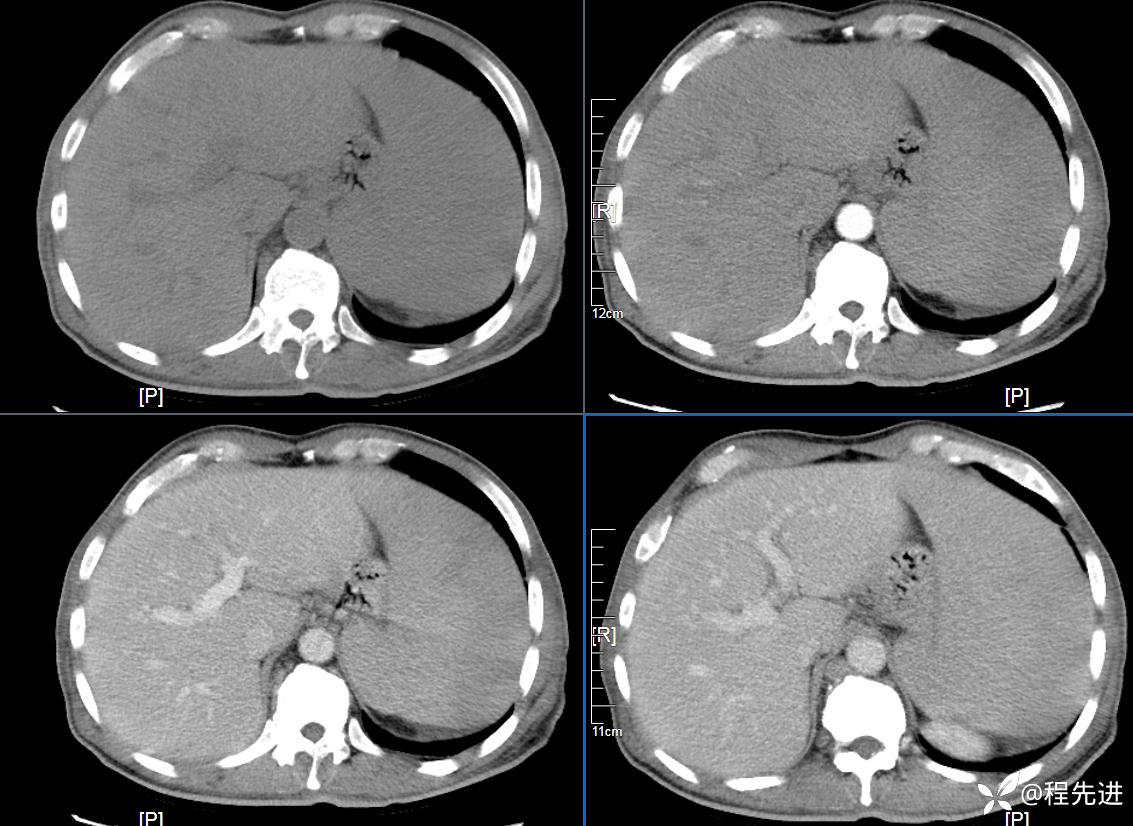

CT平扫及增强3期: